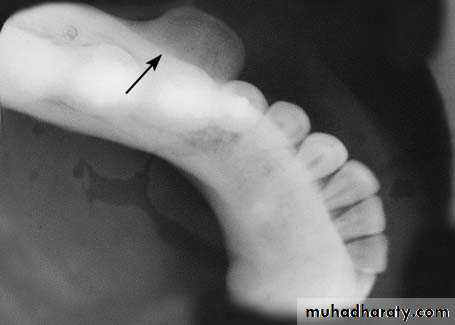

Torus MandibularisTorus mandibularis is an exostosis of unknown etiology.

It is localized in the lingual aspect of the body of the mandible, either on one side or more commonly on both sides (canine & premolar region).

Clinically, it is an asymptomatic bony protuberance covered by normal mucosa. Radiographically, it presents as a circumscribed radiopacity in the area of localization.

Torus mandibularis is completely innocent in nature and does not require any therapy whatsoever, except in cases where complete dentures are to be constructed.